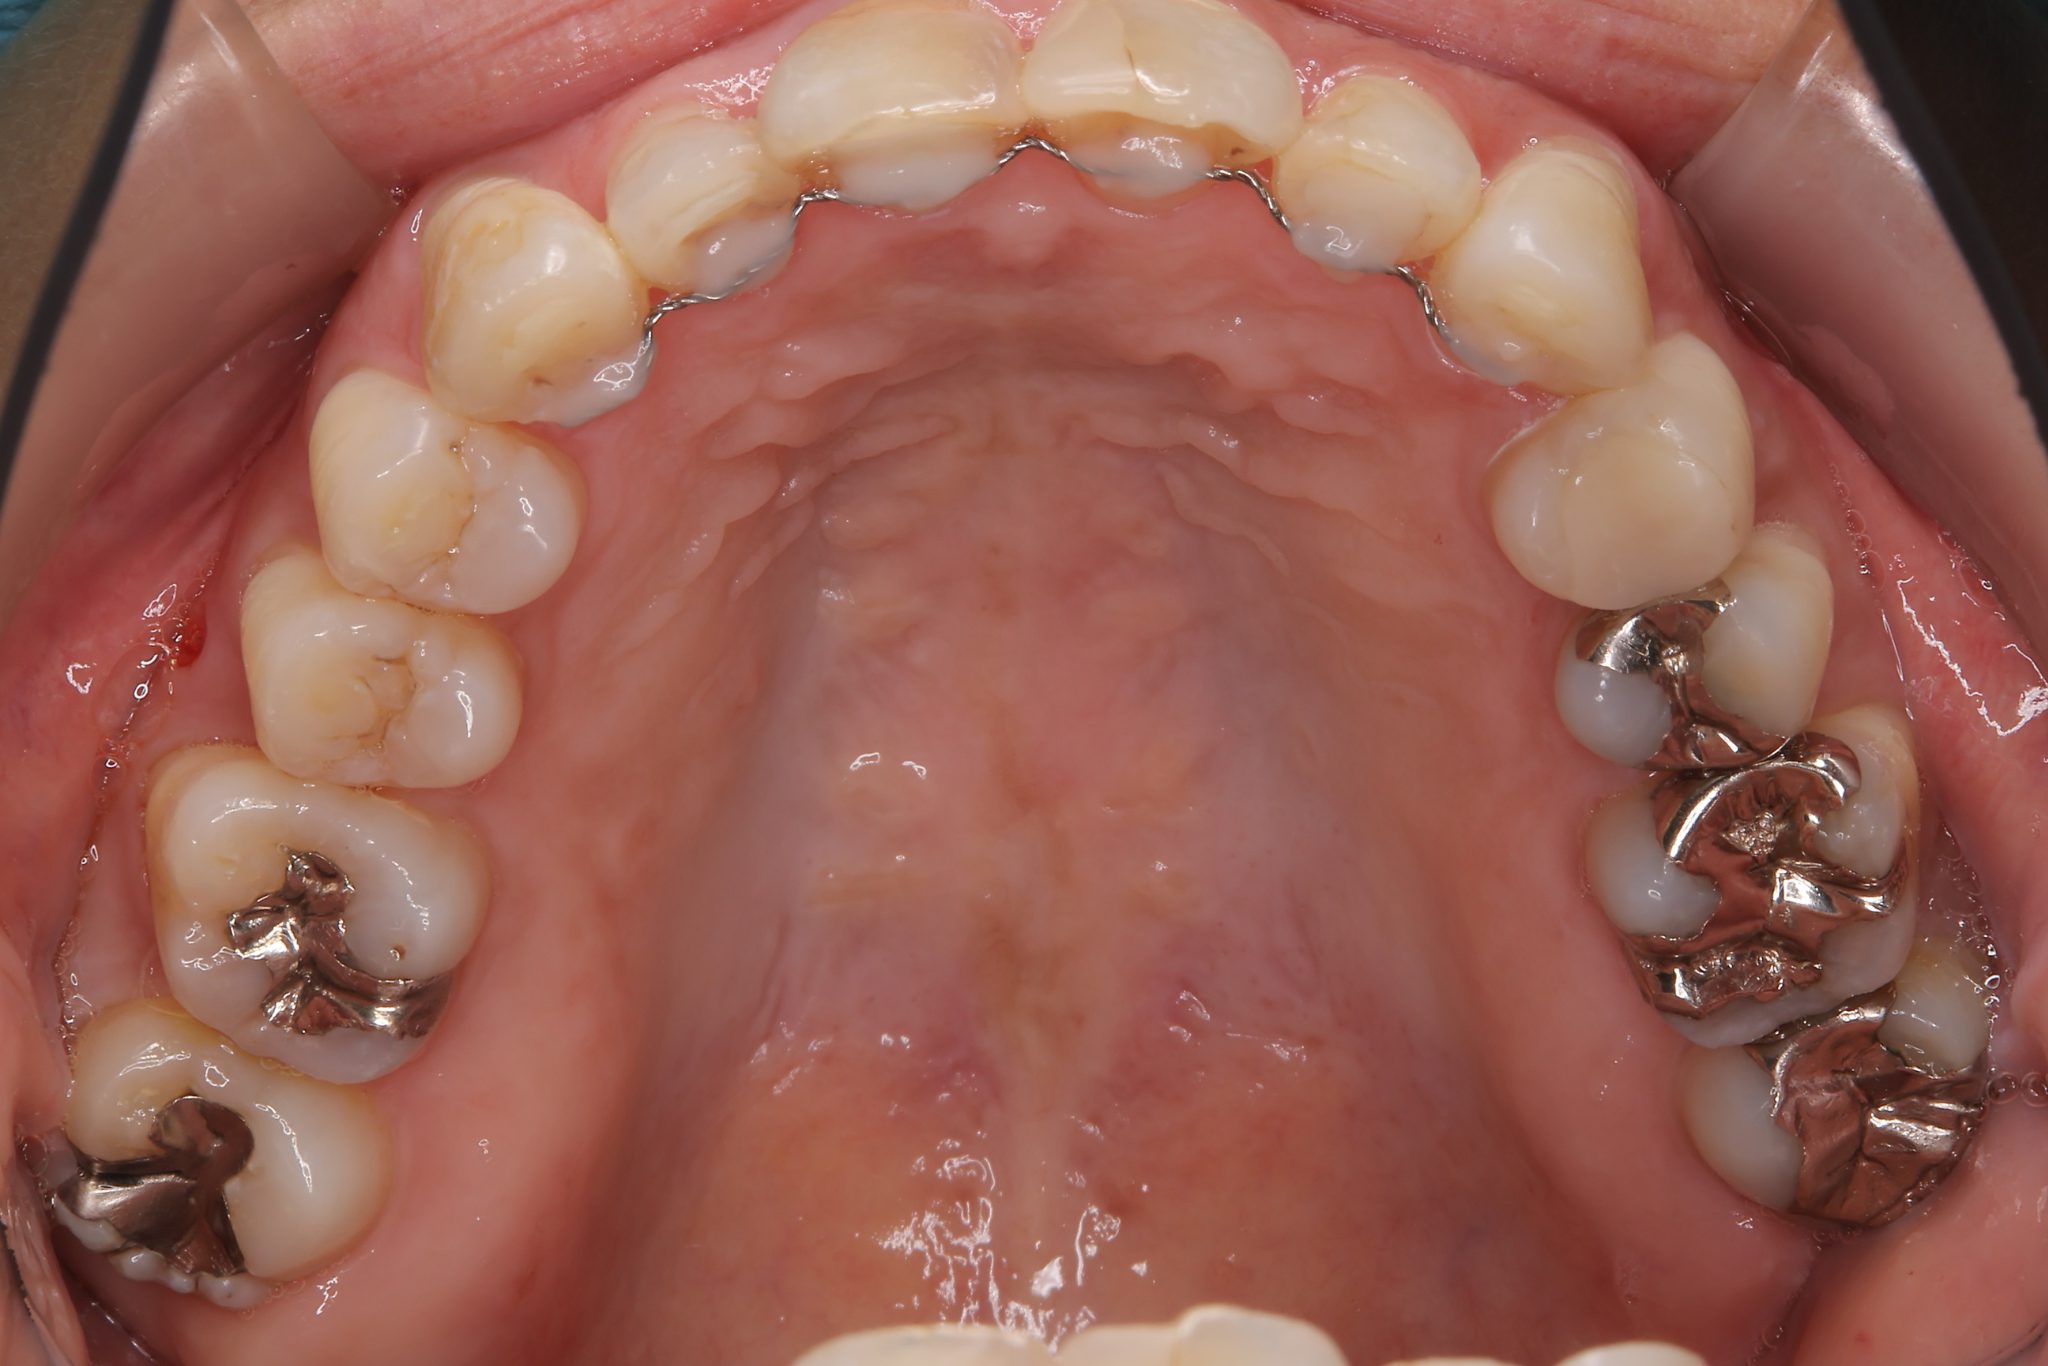

ビフォー

インビザライン矯正治療|症例_649